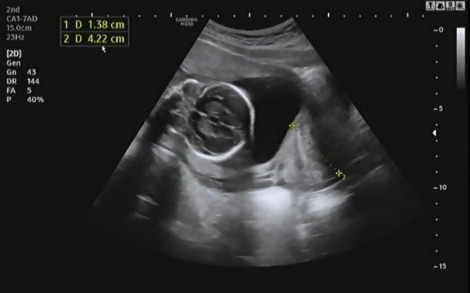

침대에 누워 복부초음파를 보는데 먼저 자궁경부 길이 등을 확인하고 양수량이 적당히 있는지 확인을 했다. 다행히 나는 자궁경부 길이가 4.22cm고 양수량도 적당히 있어서 조산위험이 없다고 했다. 자궁경부 길이가 짧을수록 조산위험이 크기 때문에 절대 안정이 필요하다.